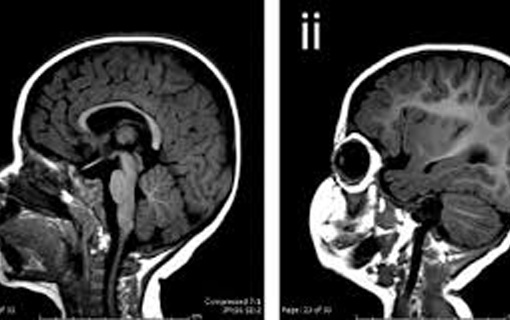

Novo estudo científico reforça a relação do vírus zika com a epidemia de microcefalia registrada no Brasil em 2015. O trabalho examinou crianças nascidas com microcefalia e sem a malformação e concluiu, por exames laboratoriais, que a infecção pelo vírus zika tem conexão direta com os casos de crianças com microcefalia.

Publicado na revista científica The Lancet, o estudo traz, pela primeira vez, resultado preliminar de um trabalho de caso-controle realizado no Brasil. “Esta análise preliminar mostra uma forte associação entre microcefalia e confirmação laboratorial de infecção pelo vírus zika”, escrevem os autores.